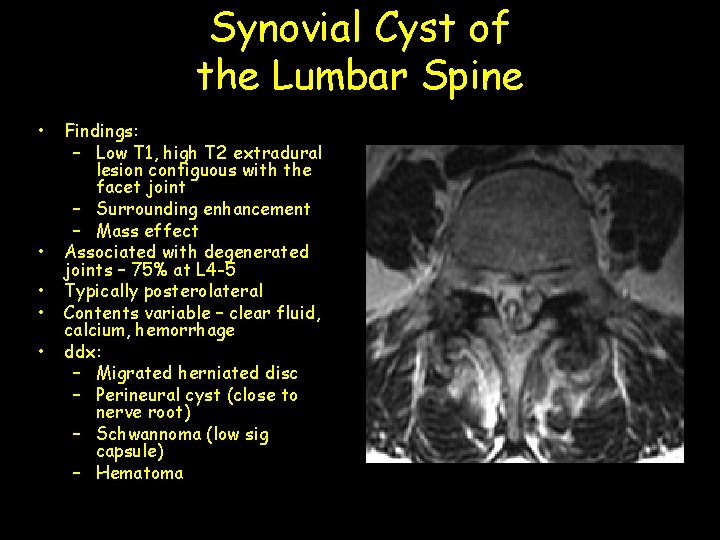

Synovial Cyst of the Lumbar Spine • • • Findings: – Low T 1, high T 2 extradural lesion contiguous with the facet joint – Surrounding enhancement – Mass effect Associated with degenerated joints – 75% at L 4 -5 Typically posterolateral Contents variable – clear fluid, calcium, hemorrhage ddx: – Migrated herniated disc – Perineural cyst (close to nerve root) – Schwannoma (low sig capsule) – Hematoma